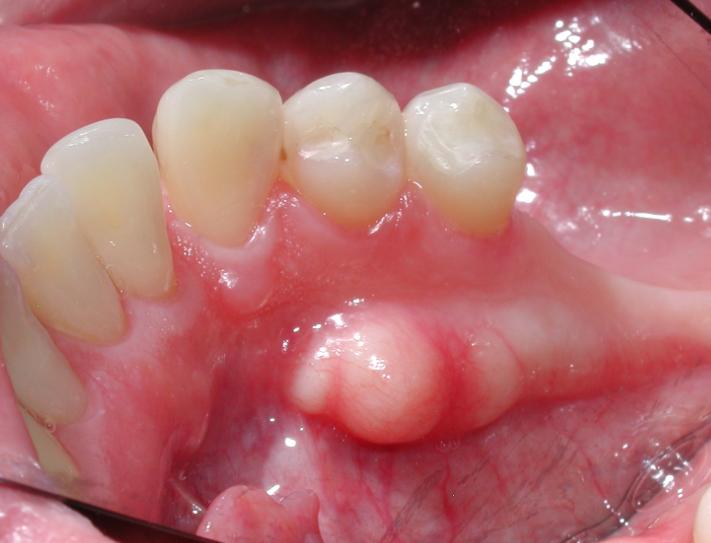

下顎骨隆起(torus mandibularis)は、下顎骨体部舌側、特に小臼歯部付近に生じる限局性の骨性隆起であり、多くは両側対称性にみられる良性の外骨症です。通常は無症候性で治療を要しませんが、義歯装着や粘膜外傷の原因となることがあります。発生学的に下顎骨は第一咽頭弓由来で、神経堤細胞から分化した間葉が膜内骨化によって形成されます。この膜内骨化骨は皮質骨優位で、機械的刺激への応答性が高いという特性をもちます。骨形成の分子基盤には、BMP–Runx2–Osterix軸が存在し、BMPがRunx2を活性化して骨芽細胞分化を誘導します。FGFシグナルは前駆細胞の増殖と分化バランスを調整します。

下顎骨隆起(torus mandibularis)と食いしばりや歯ぎしり(ブラキシズム)との関連が示されています。ブラキシズムでは咬合力が持続的・反復的に増大し、咬合応力が下顎体皮質骨へ直接伝達されます。とくに小臼歯部舌側は応力集中部位であり、骨膜や皮質骨表層に機械刺激が加わります。この刺激はメカノトランスダクション機構を介してBMP発現やRunx2活性を局所的に上昇させ、骨芽細胞活性を亢進させます。その結果、緩徐な骨付加が生じ、外骨症として顕在化します。

下顎骨隆起は、発生期に確立された膜内骨化の分子プログラムが、成人後も咬合機能負荷に応答して再活性化された結果と理解できます。腫瘍性増殖ではなく、力学的適応に基づく制御された骨形成亢進です。顎顔面骨が神経堤由来で高い可塑性をもつこと、そしてブラキシズムがその可塑性を形態変化として可視化することを示す代表的現象と考えられます。